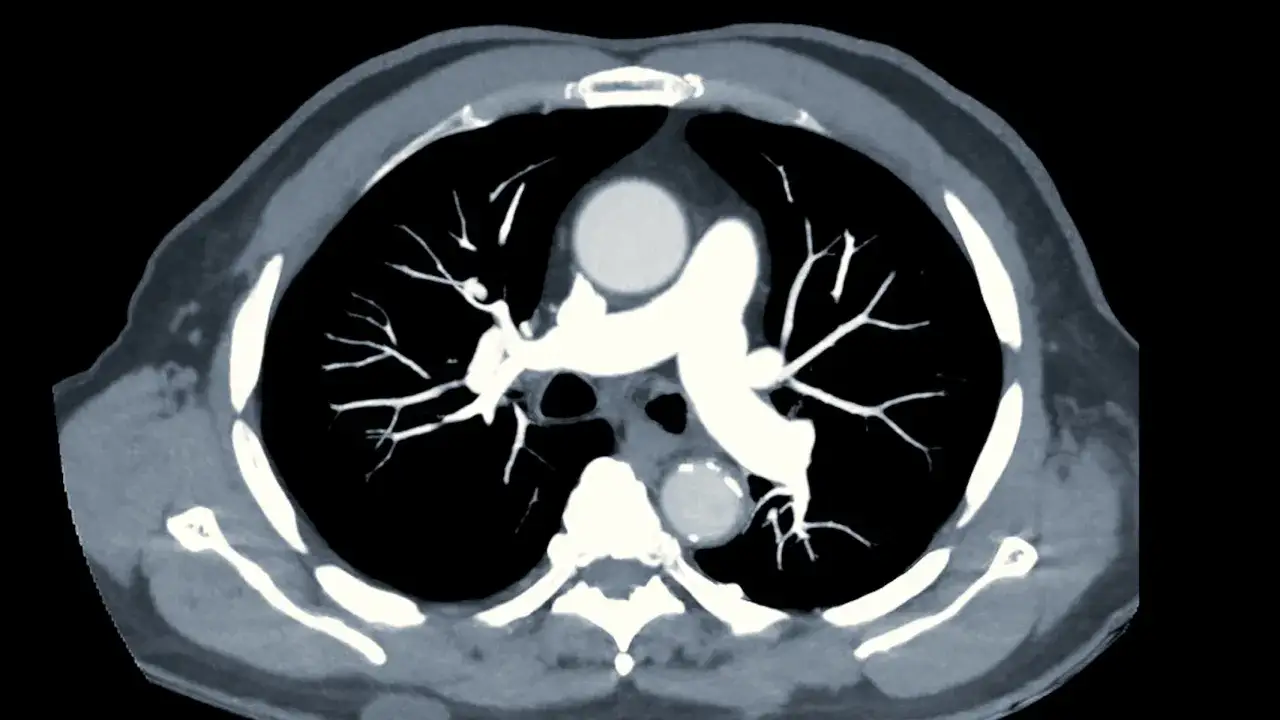

Jeśli pojawiają się objawy sugerujące zator, w diagnostyce zatorowości płucnej bardzo ważne miejsce zajmują badania obrazowe, szczególnie angio-TK, czyli tomografia z kontrastem oceniająca naczynia płucne i obecność zatoru tętnicy płucnej. Niezależnie od tego, gdzie wykonuje się diagnostykę, decyzję o badaniach zawsze powinien podejmować lekarz na podstawie objawów i ryzyka.

- Angio-TK - tomografia komputerowa klatki piersiowej jest jednym z podstawowych badań, bo pokazuje skrzepliny w świetle naczynia i ocenia płuca oraz inne możliwe przyczyny objawów.